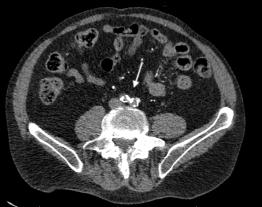

375 A Man with Sudden Onset Leg Pain and Weakness

J DeChiara, L Skinner

6.RudralingamV,FootittC,LaytonB.Ascitesmatters. Ultrasound. 2017;25(2):69–79.

7.BarrosLL,daSilvaJC,DantasACB,etal.Peritoneal Chlamydia trachomatis infectionasacauseofascites:adiagnosisnottobemissed. CaseRepGastroenterol. 2021;15(3):898–903.